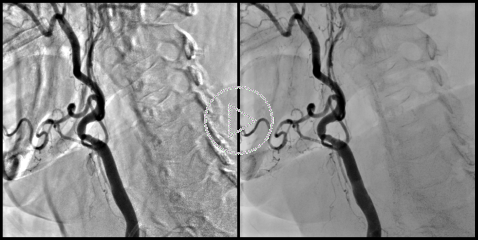

Motion Compensated DSA:

Motion Compensated DSA essentially uses the same algorithms as the Cardiac DSA. Elastic registration of the subtraction mask allows for substantial reduction of motion artifacts. The images on the left show a comparison between the "classic" (rigid) DSA without motion compensation (left image) and the Motion Compensated DSA (right image). Both images were produced with suppression of the "background" anatomy set to 75%.